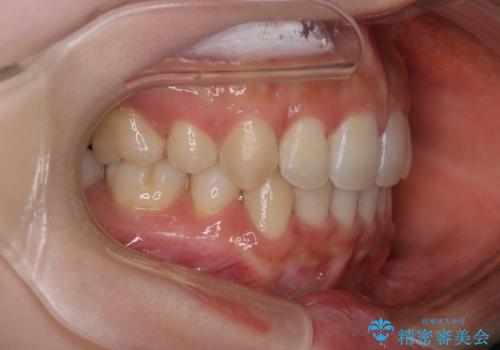

- 口元をさげたいという主訴で来院されました。4番の歯を4本抜歯し、審美装置にて治療をしました。

抜歯をしたことで口元の突出感が改善しました。約2年を予定していた矯正ですが、約1年という短い期間で終了できました。